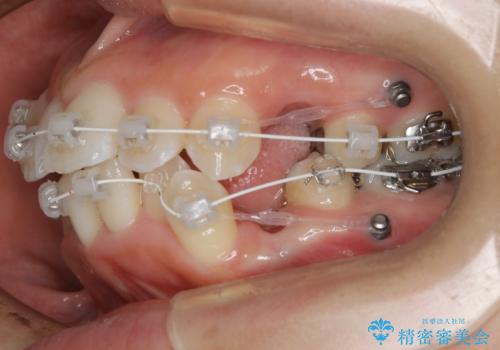

- 歯のガタつきと出っ歯が気になるので矯正治療を希望し来院された患者様です。

上下顎とも歯を並べられるスペースが無く、口元を下げたいというご希望だったので、抜歯とワイヤー矯正を併用した治療を計画しました。

抜歯スペースを利用し口元を大きく下げることが出来ました。